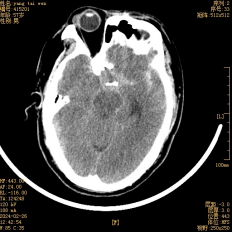

術(shù)后復查頭顱CT提示:顱腦結構正常,顯示清楚,環(huán)池、側裂池及縱裂池蛛網(wǎng)膜下腔出血明顯減少(術(shù)中進(jìn)行了清除),動(dòng)脈瘤夾位置良好(如箭頭所示)。